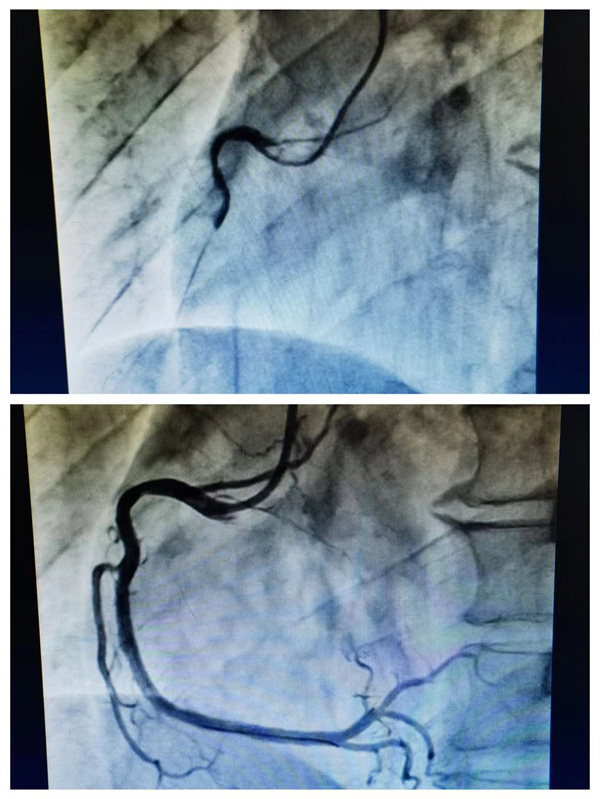

患者术前术后造影对比

19日上午10点左右,患者李华(化名)无明显诱因突发胸痛,疼痛放射至左肩背部,约1小时后情况加重,大汗淋漓,面色苍白,有呕吐症状,在邻居的帮助下拨打120后,沙湾区人民医院出车,并于10点40分进行首次医疗接触,10点47分完善首份心电图,10点48分初步诊断为“急性下壁ST段抬高型心肌梗死”。因考虑心梗,需尽快开通血管,经与患者家属沟通同意后,于11点27分到达乐山市人民医院,此时,乐山市人民医院胸痛中心急诊介入的医护团队已经准备就绪,患者直达导管室,经过副主任医师周薇、主治医师王玫苏的迅速操作,11点50分,导丝顺利通过患者“罪犯血管”,并置入1枚支架至右冠中段。D2W用时仅23分钟。术后患者迅速转危为安,胸痛症状明显改善,康复良好。